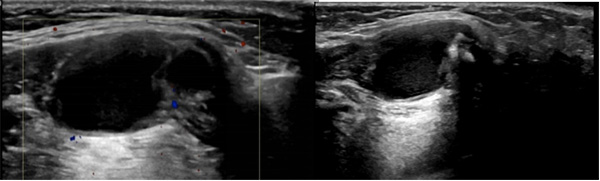

甲状舌管囊肿典型的超声表现为:

⑴ 颈前正中圆形/类圆形囊性结节,边界清,多为单发,包膜完整、囊壁薄而光滑、后方回声增强;囊肿内容物多为粘液样或胶冻样物质,故内部回声常为低弱回声;

⑵ 伴有感染时囊壁厚、不规则,囊内可见较密集的细小点状回声;

⑷ 囊肿内部无血流信号;当合并感染时,边缘可显示较丰富血流信号。